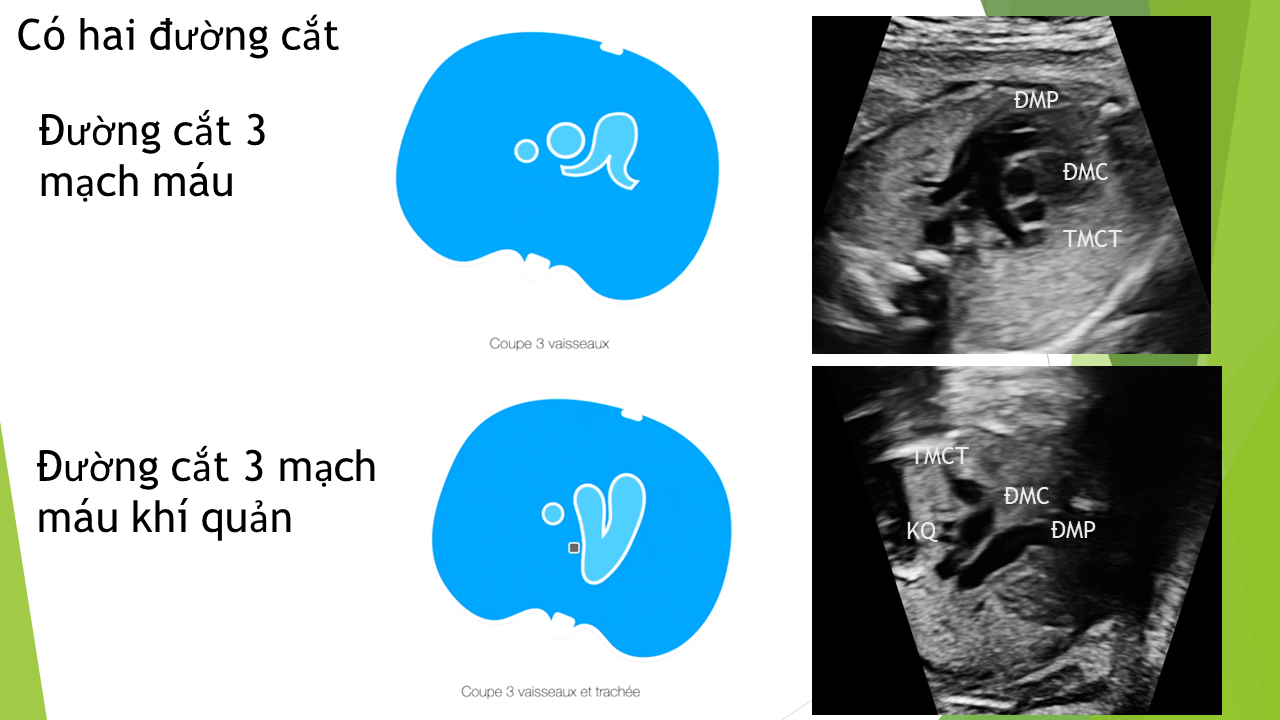

Siêu âm tim thai bằng phương pháp LEVY và STOS. 5-4-3-2-1